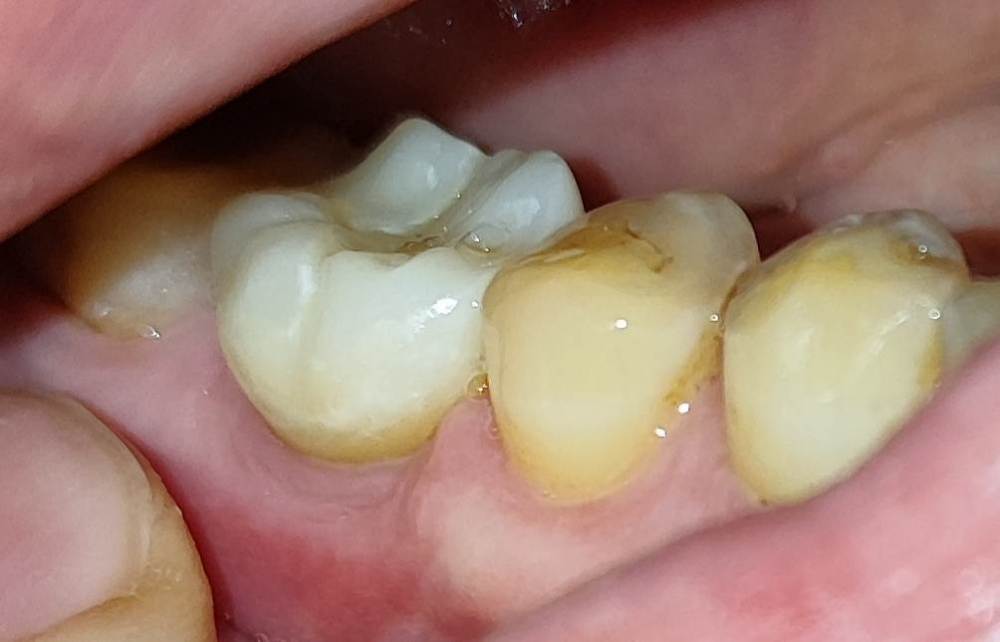

MariiaF Опубликовано 1 июня, 2023 Автор Поделиться Опубликовано 1 июня, 2023 Здравствуйте! Пришлось делать новый всё-таки снимок, ну и фото коронки без него не было смысла постить. https://hostingkartinok.com/show-image.php?id=cc02827df76c9979c8e2128519ca6cae https://hostingkartinok.com/show-image.php?id=bac696444a539cc3af276d4215e62264 прямо на сайт не выкладывается, опять Ссылка на комментарий

АнтонТЛТ Опубликовано 1 июня, 2023 Поделиться Опубликовано 1 июня, 2023 По рентгену складывается впечатление, что коронка как будто немного перекошена (это если прям выискивать к чему предраться). По фото видно, что десна немного воспалена. Анатомия бугров коронки выглядит очень выраженной, если сравнивать со стираемостью соседних зубов. Ссылка на комментарий